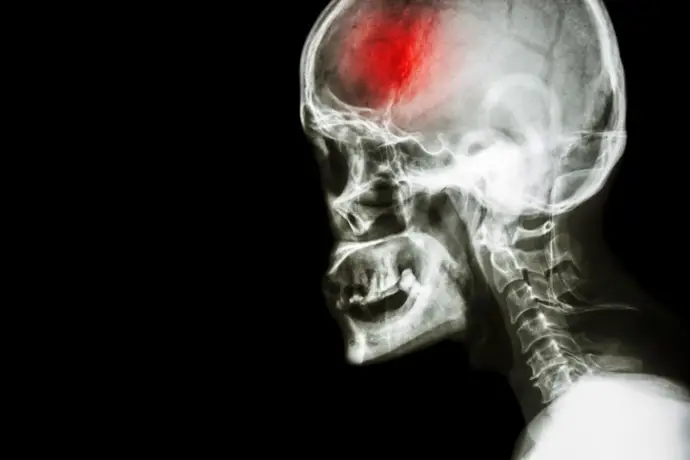

En un avance prometedor para la medicina regenerativa, un equipo internacional de científicos ha encontrado una nueva vía para ayudar al cerebro a recuperarse de lesiones graves como derrames y conmociones cerebrales, utilizando células madre. Este enfoque innovador busca reconstruir circuitos neuronales dañados mediante el trasplante de células madre, lo que abre nuevas posibilidades en el tratamiento de daños cerebrales.

Es importante señalar que, a diferencia de otros tejidos del cuerpo que se recuperan rápidamente, como la córnea, el cerebro es un órgano que presenta grandes dificultades para regenerarse. Las células cerebrales adultas son estables y pueden durar toda la vida, salvo en casos de traumas o enfermedades.

El principal reto de las terapias de medicina regenerativa para el ictus y otros tipos de daño cerebral es la falta de un entorno adecuado para el crecimiento celular. El cerebro en desarrollo proporciona las condiciones óptimas para las células madre, mientras que el cerebro adulto después de un ictus se convierte en un paisaje hostil lleno de inflamación y tejido cicatricial.